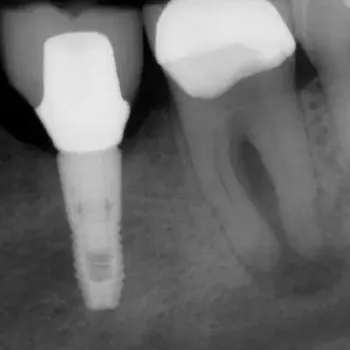

Fall 1: Revisionsbehandlung

Ausgangssituation